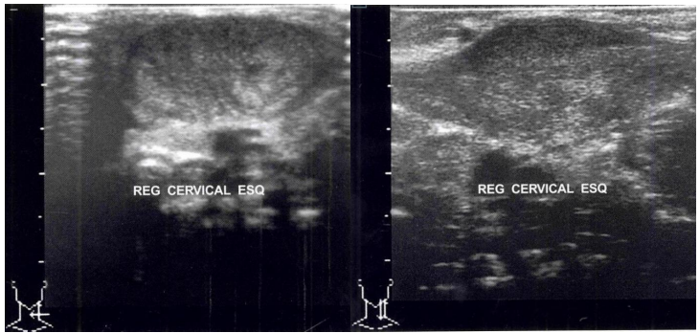

antes, sem sintomas associados. Ao exame físico destaca-se assimetria cervical com limitação na

rotação cervical à esquerda e massa com 3 cm na região latero-cervical esquerda (zona III), dura,

imóvel e indolor. Foi solicitado ultrassonografia e foi observado tais aspectos de imagem.

Considerando as imagens observadas ao ultrassom e a história clínica do paciente, o diagnóstico mais

provável é: